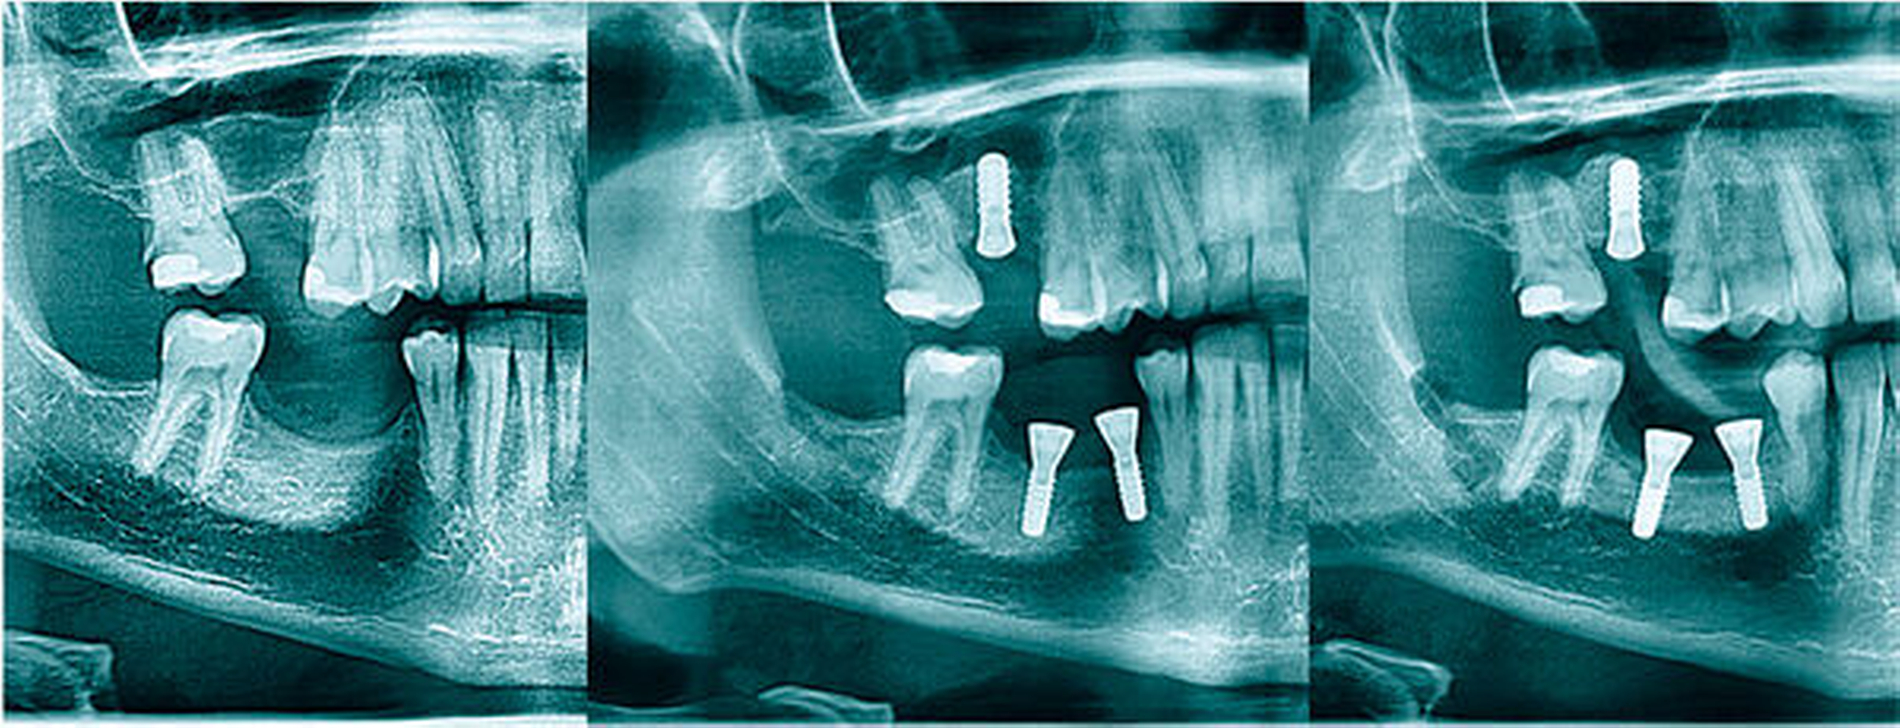

In den Abbildungen 6 bis 9 sind mehrere Fälle mit langem Beobachtungszeitraum dargestellt. Beachtenswert ist vor allem der zu beobachtende vollständige Umbau des Knochens inklusive der Ausbildung einer neuen Kompakta. Die augmentierten Bereiche sind nach wenigen Jahren nicht mehr als solche zu erkennen. Die Arbeit mit autologem Knochen ist insbesondere für die Patientengruppe interessant, die bevorzugt nach biologisch sicher verträglichen Behandlungen sucht. Dieser Trend nimmt unseren Beobachtungen nach stetig zu. n

In den vergangenen 19 Jahren wurden vom Koautor dieses Beitrags 900 externe Sinuslifts mit autologem Knochen in unserer rein ambulanten Klinik durchgeführt. Eine Auswertung der Daten zeigte primäre Misserfolgsraten von circa 1 Prozent. Wir konnten dreimal eine Verlagerung des Implantats in die Kieferhöhle beobachten, jeweils bei einer Restknochenhöhe unter 1 mm. Bei all diesen Fällen handelte es sich um einen doppelseitigen Sinuslift. Wir vermuten eine zu starke und zu frühe Belastung bei der Nahrungsaufnahme. Aus diesen Gründen sehen wir inzwischen bei dualen Sinuslifts und sehr geringer Restknochenhöhe von einem einzeitigen Vorgehen ab.

Bislang mussten wir acht unserer Implantate aufgrund einer zu weit fortgeschrittenen Periimplantitis entfernen. In drei dieser Fälle konnte ohne erneute Augmentation implantiert werden. Misserfolge bestehen in der Regel aus einer fehlenden Osseointegration der Implantate bei einem einzeitigen Vorgehen. Meist war die eigentliche Knochenaugmentation trotz der Implantatabstoßung erfolgreich, so dass eine erneute Implantation ohne Augmentation möglich ist. Die Reimplantation erfolgt nach der abgeschlossenen Durchbauung des Transplantats.

In OPGs von Fällen, in denen rein autolog transplantiert wurde, fällt unter Umständen eine Sinterung des Knochens um die Implantatspitze auf. Eine frühe Belastung der Implantate kann diesem Vorgang entgegenwirken. Die Hauptbelastung beim Kauvorgang trägt bekannterweise der Knochen im koronalen Drittel des Implantats, der Druck lässt Richtung apikal immer mehr nach [Himmlová et al., 2004]. An der Implantatspitze erfährt der Knochen unter Umständen dann keinerlei Belastung mehr und atrophiert dementsprechend, was jedoch zu keiner Verschlechterung der Prognose führt. Betont werden muss, dass diese „Inaktivitätsatrophie“ unsere persönliche Hypothese ist. Auch in der Literatur konnte allerdings bisher kein negativer Effekt auf die Implantatüberlebensrate festgestellt werden [Chen et al., 2021]. Unsere Erfahrung zeigt, dass dieser Effekt ab einer Implantatlänge über 10 mm signifikant zunimmt, so dass wir inzwischen nur Implantate mit einer maximalen Länge von 10 mm verwenden.